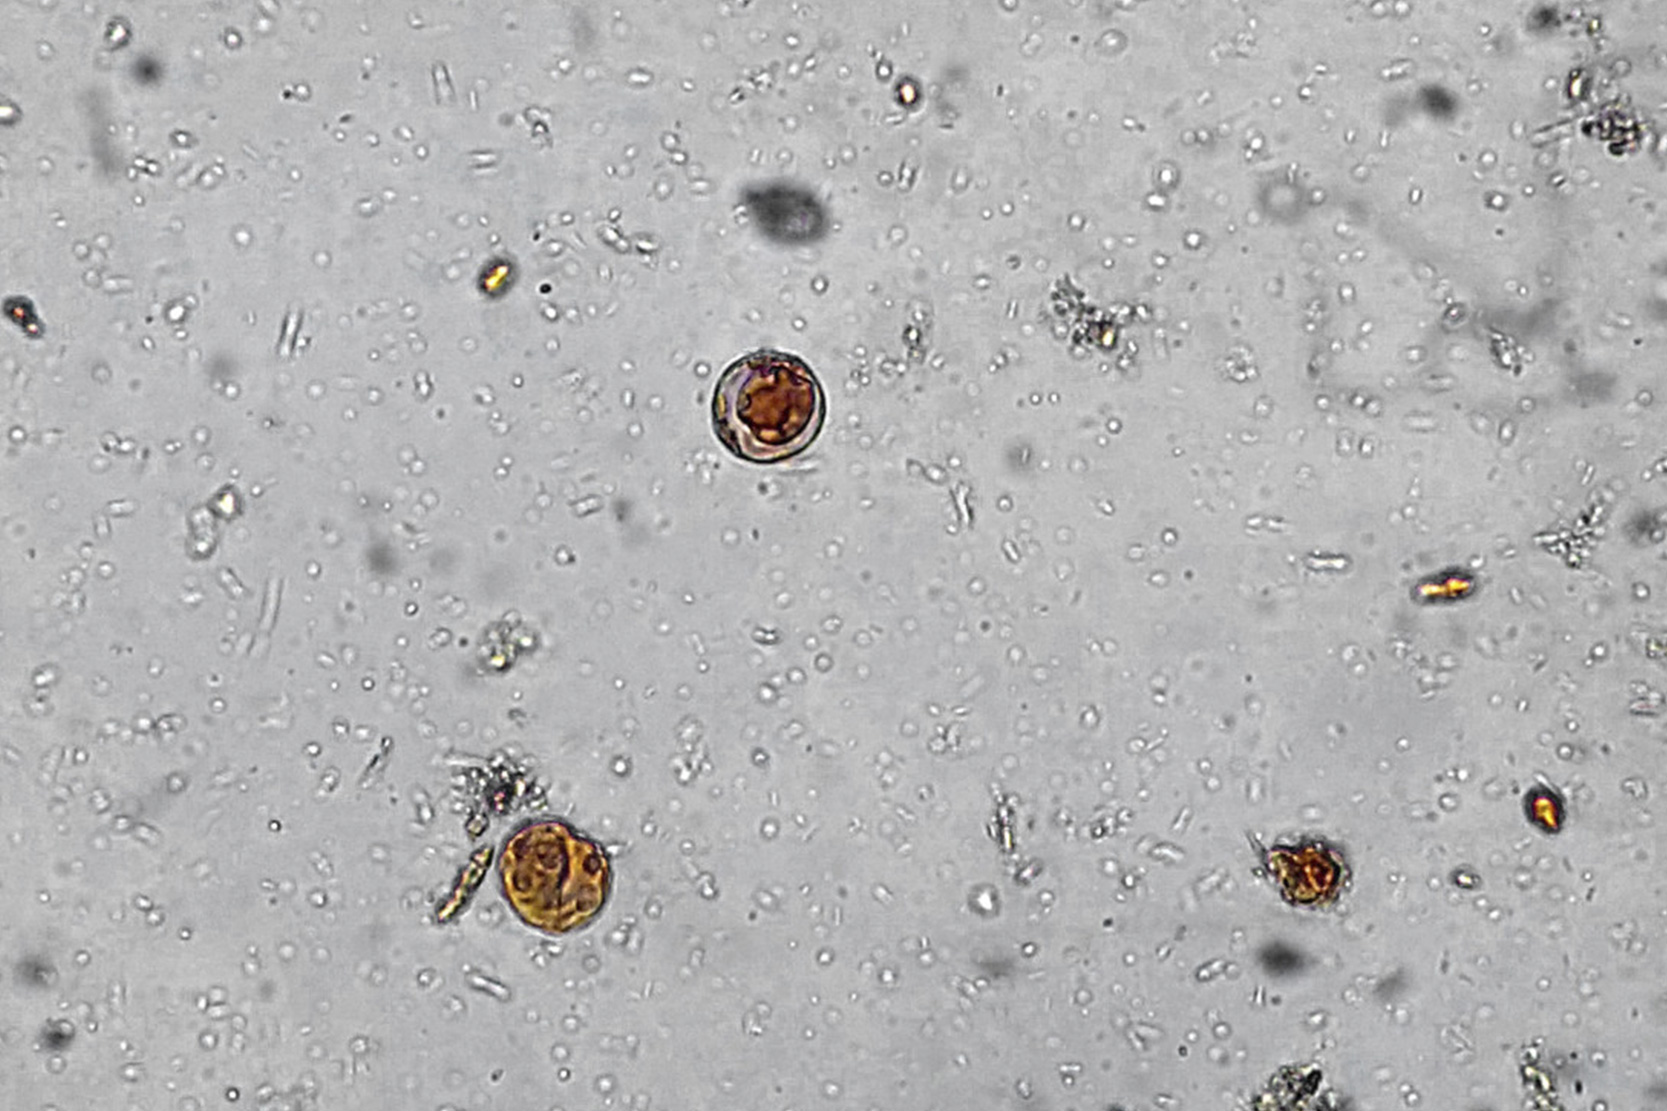

B. hominis es un organismo polimórfico. Están descritas cuatro formas morfológicas diferentes: vacuolar, granular, ameboide y quistica. Además se han observado otras morfologías entre las que destacan las formas avacuolares y multivacuolares que posiblemente son fases intermedias. La forma vacuolar tiene un tamaño muy variable, entre 2-200 μm de diámetro con una media de 4-15 μm y se caracteriza por la presencia de una gran vacuola central, implicada en el almacenamiento de carbohidratos y lípidos, que ocupa aproximadamente el 90% del volumen celular. En la periferia se encuentran el citoplasma con mitocóndrías, aparato de Golgi y retículo endoplasmático y varios núcleos (generalmente más de 6). Esta forma predomina en las heces frescas y puede observarse en los cultivos.

Formas vacuolares de Blastocystis hominis

La forma granular parece proceder de la transformación de la vacuolar por diferentes estímulos como concentración de suero en medios de cultivo, subcultivo, presencia de antibióticos, etc. Es morfológicamente similar a la forma vacuolar pero el citoplasma circundante o la vacuola (más frecuentemente) están finamente granulados.

La forma ameboide es polimorfa, capaz de emitir pseudópodos por extensión y retracción y con una marcada actividad fagocitaria demostrada por la presencia de restos bacterianos y celulares en su interior. En este sentido se ha sugerido que es una fase intermedia entre la forma vacuolar y la quística y estaría encargada de la fagocitosis para obtener energía para la enquistación Es la forma predominante en los cultivos fundamentalmente si las heces proceden de pacientes sintomáticos por lo que se especula que puede ser un indicador de patogenicidad o contribuir a la patogenicidad de Blastocystis hominis.

La forma quística se ha descrito hace pocos años posiblemente debido a que su pequeño tamaño (3-5 μm) y apariencia hacían considerarlos como artefactos. Existen 2 tipos de quistes: fecales (forma infectante, transmisible) o de pared gruesa y quistes de pared fina responsables de la autoinducción.

Pleomorfismo de Blastocystis hominis